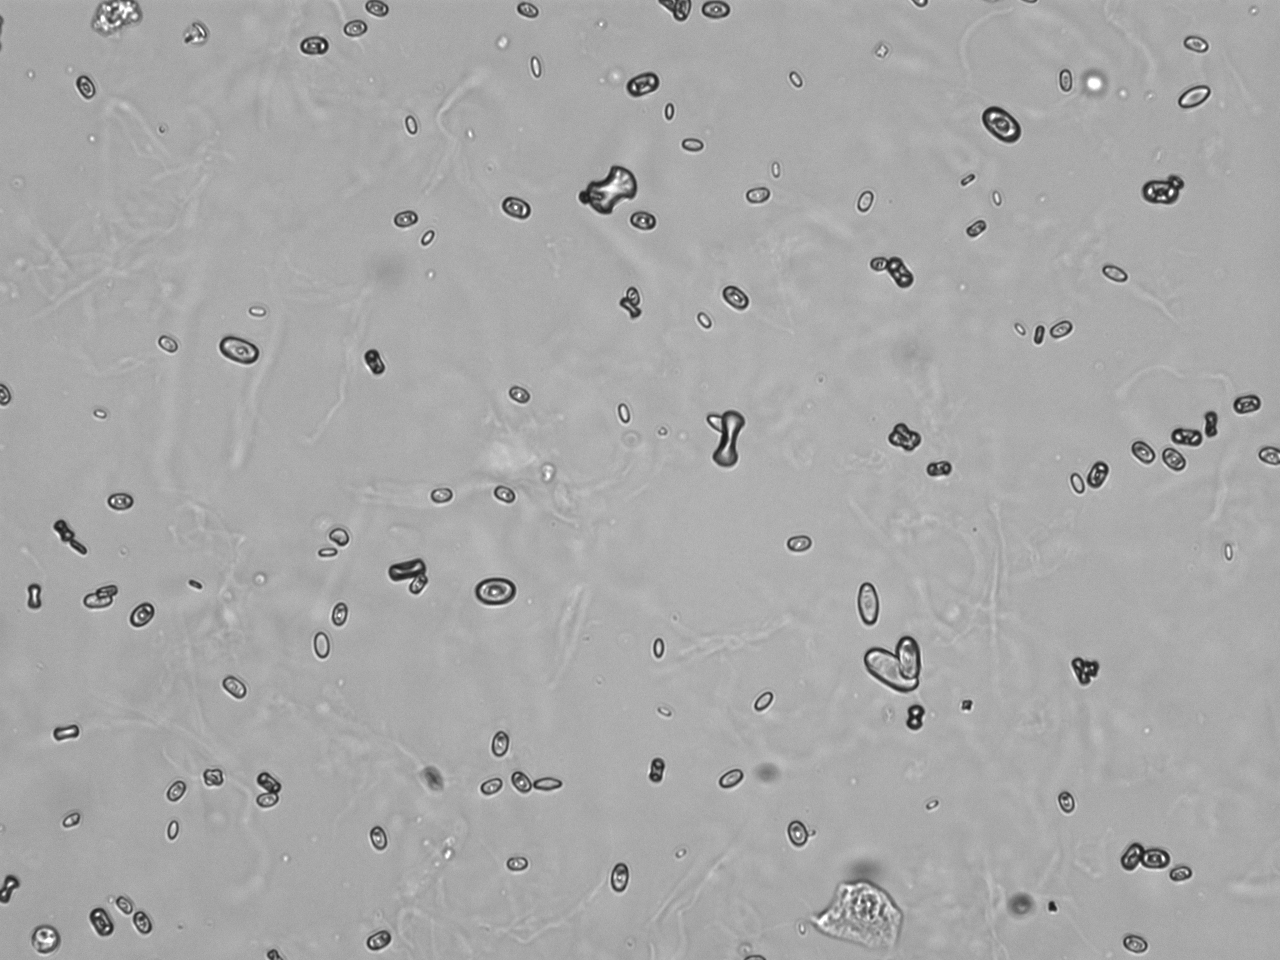

Urin-Feature: CaOxalateMonohyd